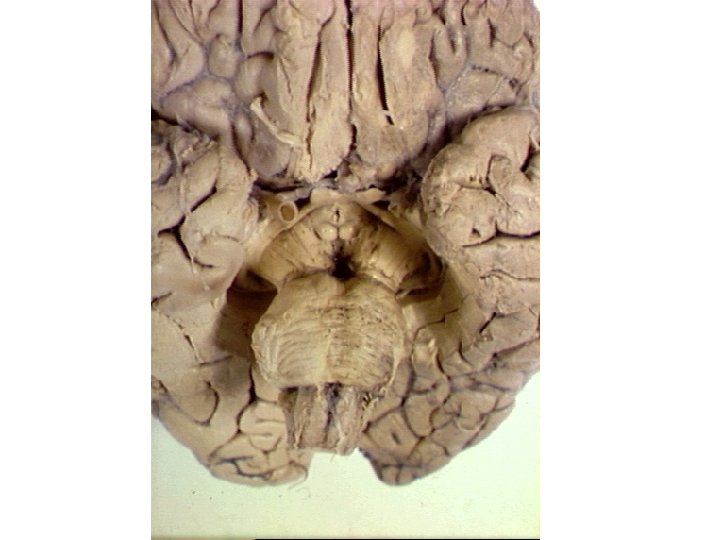

Olf system LIMBIC SYS Limbic System Limbic lobe

Limbic System: Limbic lobe + hippo. , fornix, MMBs, MTT, ant. nuc. thal. , cingulate cortex, cingulum, parahippo. gyrus then into hippo. stria terminalis? Papez circuit? Limbic Lobe